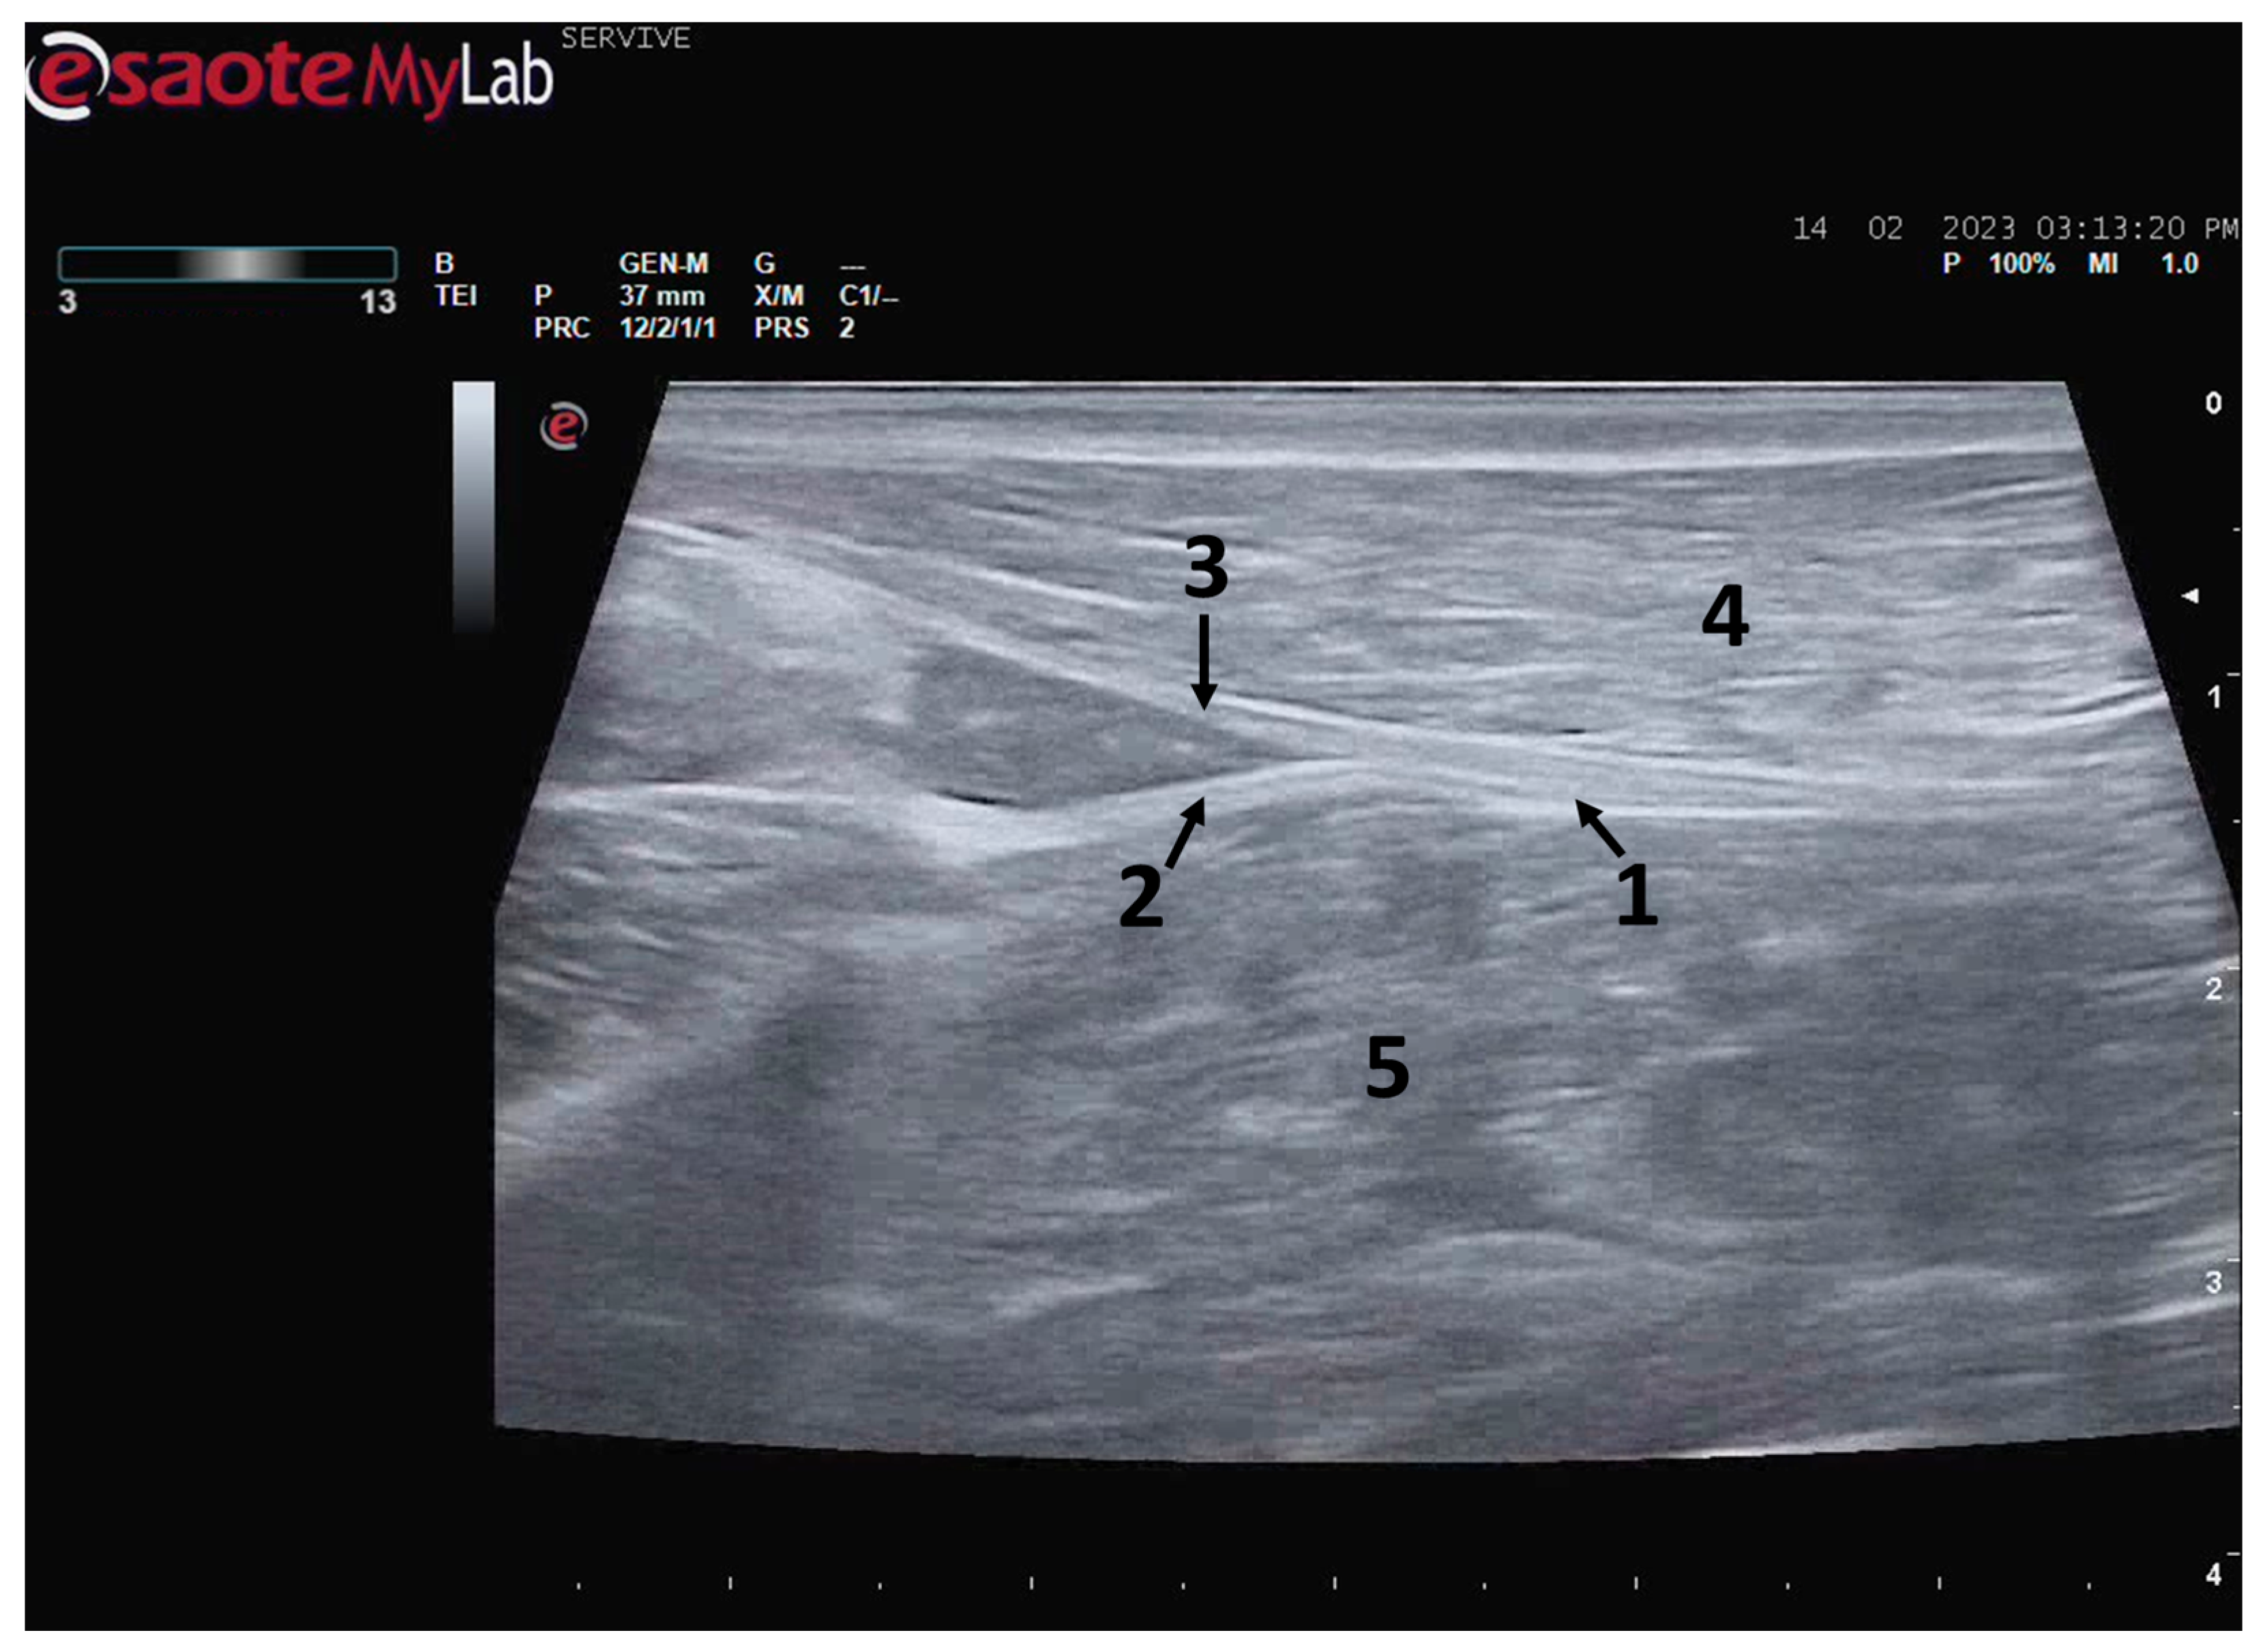

Figure 4.

Ultrasound image of the left sciatic nerve of a sheep nerve halfway through the thigh: (1) sciatic nerve, identified by an arrow (nerve fascicles enclosed by perineurium); (2) epineurium, identified by an arrow; (3) biceps femoris muscle; (4) piriformis muscle; (5) adductor muscles. DIST1 represents the measurement of the diameter of the sciatic nerve halfway through the thigh.

At the level of the stifle, and with great interindividual variation, the two branches of the sciatic nerve, the common peroneal nerve, and the tibial nerve, are easily observable and distinguishable, diverging from the main nerve (Figure 5). Both the sciatic nerve and its branches appear as hypoechogenic neuronal tubular structures (nerve fascicles and the perineurium) surrounded by a hyperechogenic envelope corresponding to the connective tissue nerve wrappings (epineurium) (Figure 3, Figure 4 and Figure 5). The most lateral nerve, appearing dorsally on the ultrasound image, corresponds to the common peroneal nerve and imagiologically has a slightly smaller diameter than the tibial nerve, which is more medial and appears ventrally on the ultrasound image. Accompanying both nerves distally, there is a tendency for a slight decrease in their diameter before the final ramifications, but the intended site for inducing injury to the common peroneal nerve is proximal to the point where the decrease in diameter occurs.